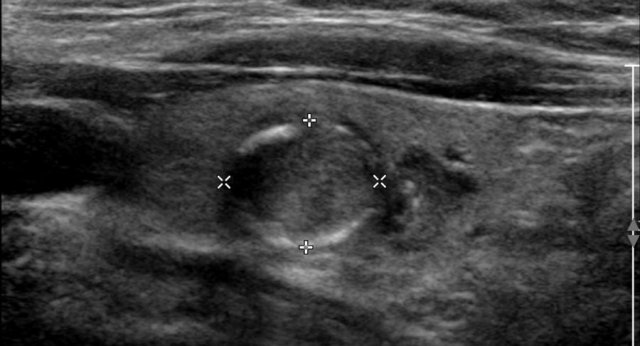

Margin

Study the image and score for TI-RADS.

Scroll the image for the TI-RADS score.

Then continue reading.

Although the margin is ill-defined on the cranial side, this still means 0 points for the margin.